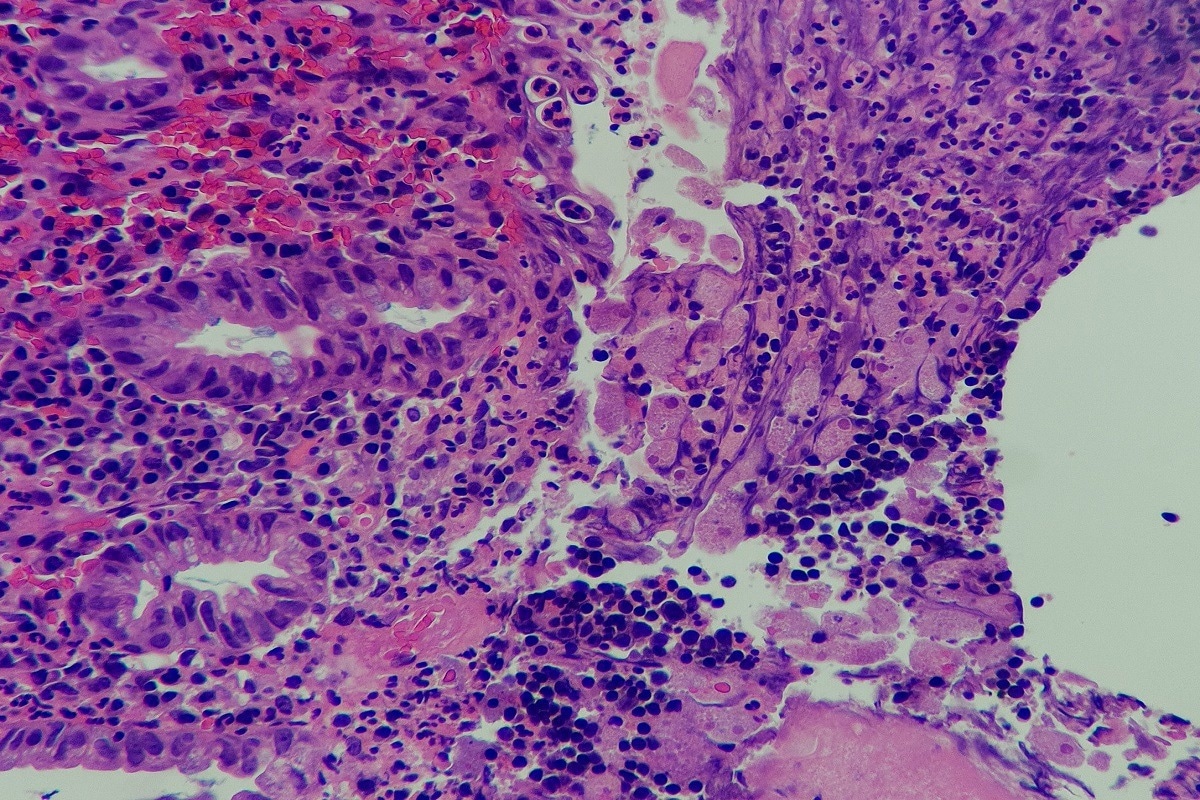

Colonoscopy and microscopic examination of biopsies are the gold standards for diagnosing amoebic colitis. The trophozoite contained within ulcers can be seen under a microscope. Patients with diarrhea are likely to have E. histolytica present in the stool. As the cecum and ascending colon are affected, histological examination of the ulcers shows flask-shaped protozoa. in severe cases, the ulcers will merge and present as ulcerative colitis.